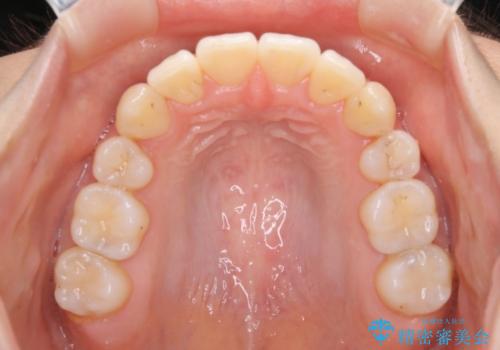

奥歯の上下のズレ等は軽度で、必要なスペースと抜歯により作られるスペースがほぼ等量だったため治療の単純化が計れ、大きな移動・見た目の劇的な変化に対して比較的早期での治療完了となりました。

叢生の度合いが重く、抜歯が必要なケース。八重歯の部分以外には大きな問題は認められなかったため、劇的変化が起こる治療でも比較的短期間で終了することができました。